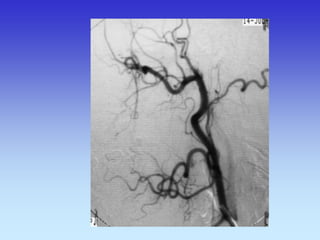

METODE PRIKAZA KRVNIH ŽILA

•UZ-DOPPLER

•DSA

•CTA

•MRA

B-mod i obojeni Doppler karotidne arterije